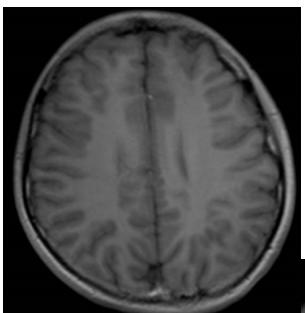

答案:Dandy-Walker畸形(变异型)

Dandy-Walker畸形典型三联征:小脑蚓部发育不良+四脑室囊样扩张+后颅窝扩大。

Dandy-Walker畸形可合并其他异常,70-90%可合并脑积水。

三联征不全,只有前两联,没有后颅窝扩大时,称为Dandy-Walker变异型。

该病例后颅窝扩张并不明显, 应该符合Dandy-Walker变异型。虽然到了周五,大家热情不减。有理有据的分析,不管是对是错,总是会有收获。